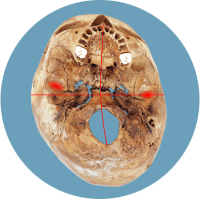

Le problème majeur réside dans la modification de la structure de la tête : la base du crâne devient asymétrique. Cela affecte principalement la position des oreilles (organes de l’équilibre), les articulations temporo-mandibulaires (malocclusion dentaire) et les vertèbres cervicales. La situation devient critique au plus tard lorsque les enfants se redressent à la fin de leur première année et développent une posture asymétrique de la colonne vertébrale.

Le déplacement des organes de l’équilibre est indiqué par les croix rouges.

Les informations erronées provenant des organes de l’équilibre déplacés ou du champ récepteur cervical influencent le traitement dans le cerveau et peuvent entraîner une mauvaise posture de la colonne vertébrale.